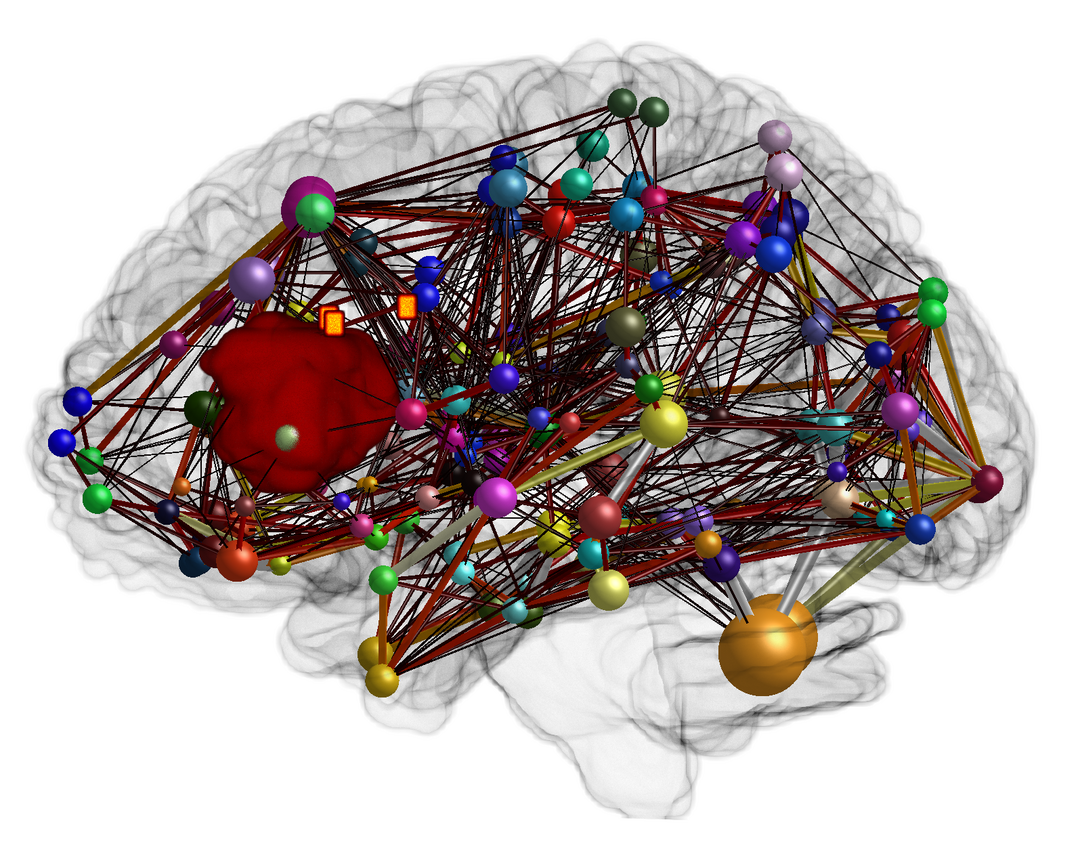

Коннектом мозга: визуализация связей и нейронных путей